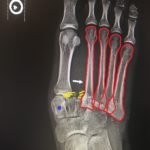

The frontal view of the right foot showed divergent dislocation of the second through fifth metatarsal bones (red outlines) consistent with Lisfranc injury. Though the Lisfranc ligament is not visualized by radiograph, the yellow markings represent the location of the Lisfranc ligament between the medial cuneiform (blue dot) and the base of the second metatarsal bone. The first metatarsal and the medial cuneiform remain congruent. The lateral view shows dorsal dislocation of the midfoot (pink circle) consistent with instability. There is associated extensive midfoot soft tissue swelling.